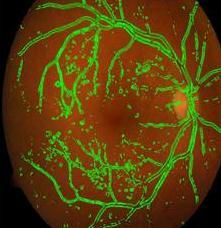

Fig. 9, 10 shows the detected blood vessels in normalandDRaffectedfundusimages.

Fig 9:DetectedBlood VesselsinaNormalRetinal FundusImage